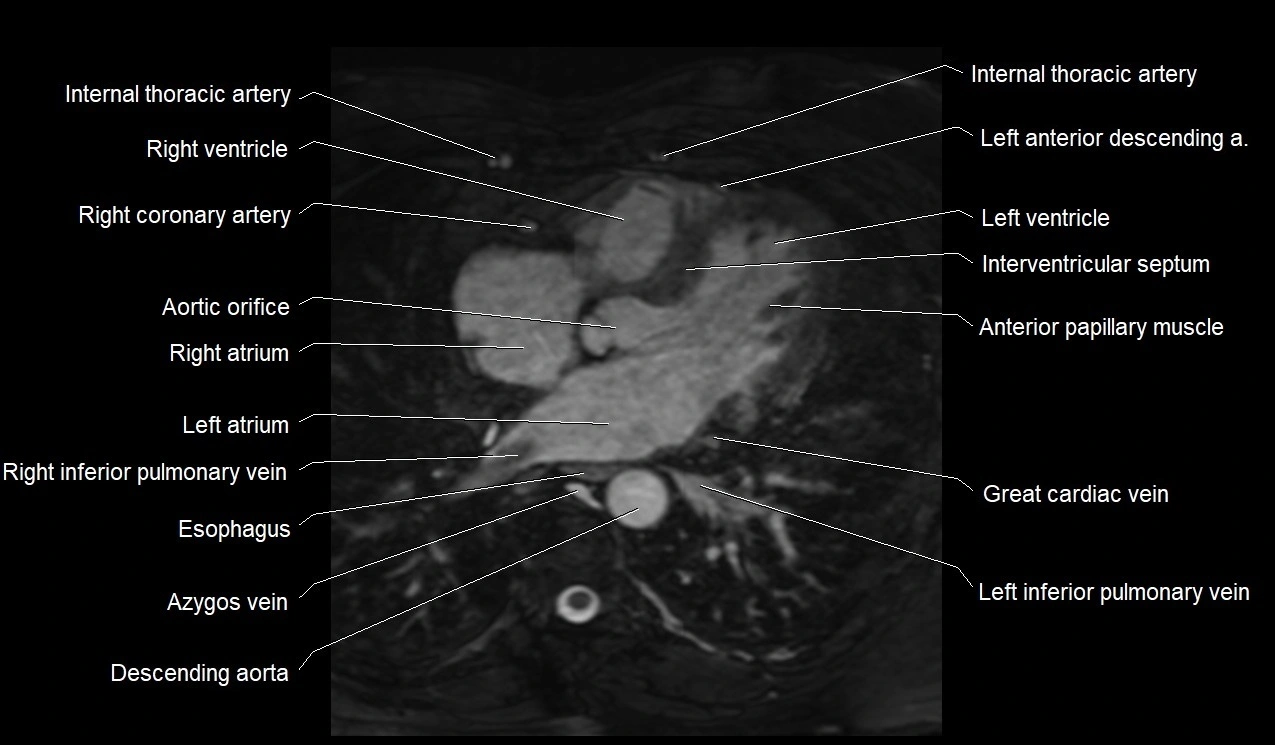

MRI image